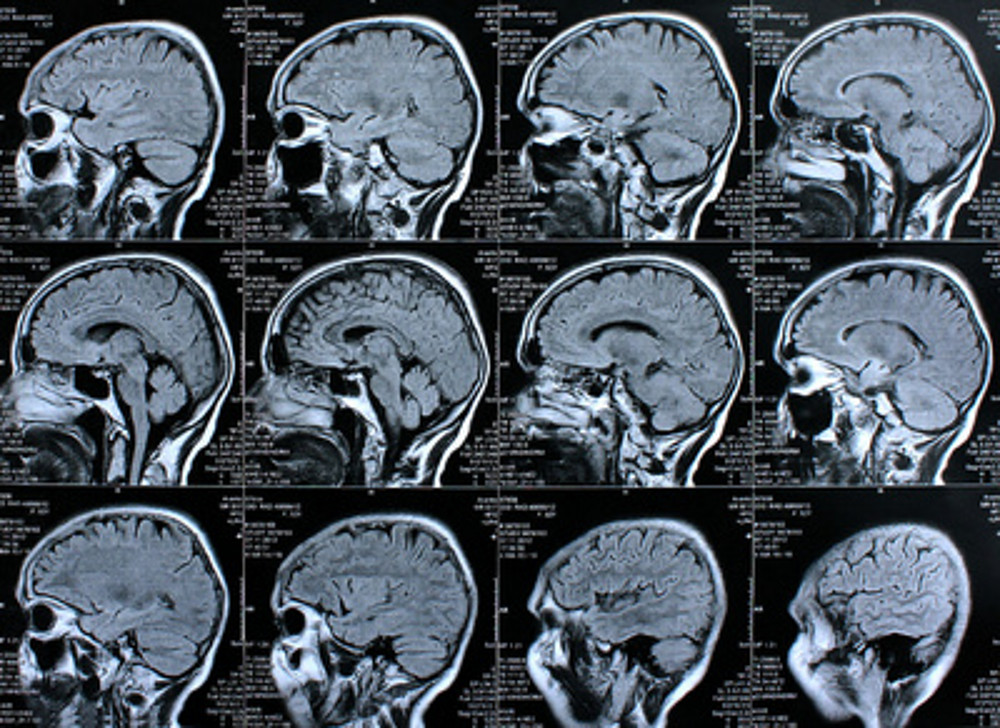

Der Alzheimer-Erkrankung auf der Spur

ForscherInnen der Universitäten Graz und Bayreuth sind den molekularen Mechanismen der Alzheimer-Erkrankung auf der Spur. Foto: Rike/www.pixelio.de

ForscherInnen gewinnen neue Einsichten in zellbiologische Prozesse

Die zellbiologischen Prozesse, die neurodegenerative Erkrankungen verursachen oder verstärken, sind bis heute nur unzureichend erforscht. Ein internationales Team um Univ.-Prof. Dr. Frank Madeo von der Karl-Franzens-Universität Graz und Dr. Ralf Braun von der Universität Bayreuth hat jetzt molekulare Zusammenhänge entdeckt, die dazu beitragen können, insbesondere die Entstehung und den Verlauf der Alzheimer-Krankheit besser zu verstehen. In der aktuellen Ausgabe der Zeitschrift „Cell Reports“ stellen die WissenschaftInnen aus Bayreuth und Graz zusammen mit PartnerInnen aus Maastricht, Freiburg und Paris ihre Forschungsergebnisse vor. Die neuen Erkenntnisse, die sie in enger Kooperation gewonnen haben, werden möglicherweise dabei helfen können, medizinische Wirkstoffe gegen die Alzheimer-Krankheit zu entwickeln.